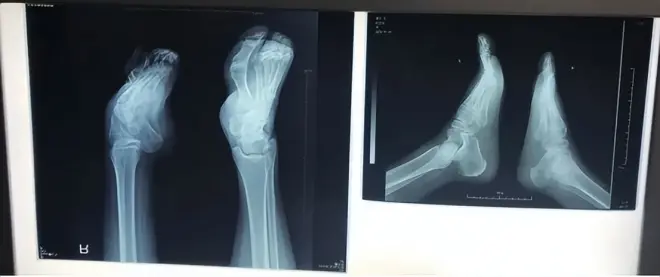

通过胡霞医生的精心治疗,大大改善了足踝畸形,实现了独立行走的梦想。今年夏天来复查,X光显示她右脚的形态明显改善,变得更加清晰明了,骨块完整无损,没有进行任何切割或内固定手术,关节也恢复了原本的位置。